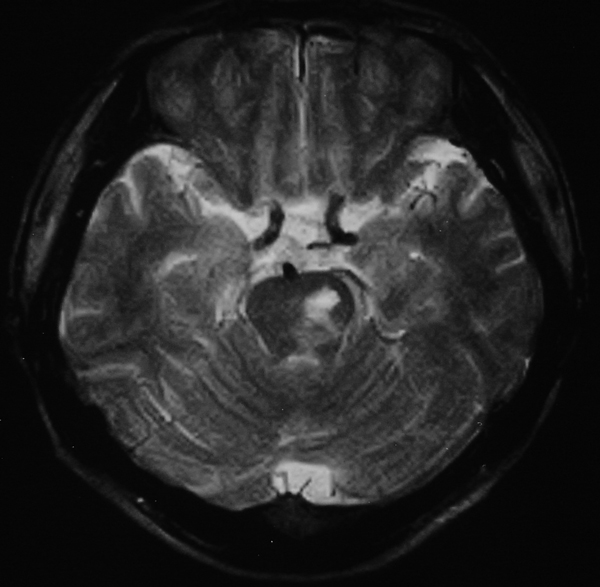

男 49岁 脑干腔隙梗塞5年。

这患者脑干(脑桥)腔隙脑梗塞是肯定的 有20002年资料 明天上传全部资料(当时工作忙 来不及)

图片质量不是很好!脑干偏左侧隐约可见低密度病灶,不知5年前怎样?单存本例支持:脑干梗塞!

1 单纯此图像定脑干梗塞依据不足. 2 可薄扫或核磁检查.

楼主是想具体分清是发生于脑桥还是中脑吧,脑桥的主要特征是结构就是小脑脚及四脑室,可以看到小脑脚及四脑室时就肯定是脑桥,中脑的主要特征就是环池,有完整的环池就是中脑,并且由于中脑短,一般只有一层可见,最多出现两层,本例层面应该是属于中脑层面,其上方应该是四叠体池及丘脑下部了.

楼主是想具体分清是发生于脑桥还是中脑吧,脑桥的主要特征是结构就是小脑脚及四脑室,可以看到小脑脚及四脑室时就肯定是脑桥,中脑的主要特征就是环池,有完整的环池就是中脑,并且由于中脑短,一般只有一层可见,最多出现两层。

不知小脑脚交叉到底另何指?中脑的病灶,应该和中脑导水管加以区别。

脑干梗塞在ct上是斑点状低密度,一般只能在桥脑或中脑才能显示,延髓是很难发现(伪影多)。mr上脑干梗塞应该是长t1长t2的斑点状表现。弥散能够发现早期梗塞灶,表现高信号。

①四脑室,脑桥平面有四脑室,中脑没有;

②环池:中脑平面有完整的环池,即前有脚间池、后有四叠体池。这是标准的om线扫描图像,如果不按om线扫描就有所变化;而桥脑没有完整环池,它前方是桥前池。

③三脑室,只要扫描基线偏移不大,看到三脑室出来同层面应该是中脑